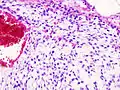

| Histopathologic image of chondrosarcoma of the chest wall. Surgical resection of recurrent mass. H & E stain. | |

Imaging studies - including radiographs ("x-rays"), computerized tomography (CT), and magnetic resonance imaging (MRI) - are often used to make a presumptive diagnosis of chondrosarcoma.[9] However, a definitive diagnosis depends on the identification of malignant cancer cells producing cartilage in a biopsy specimen that has been examined by a pathologist. In a few cases, usually of highly anaplastic tumors, immunohistochemistry (IHC) is required.